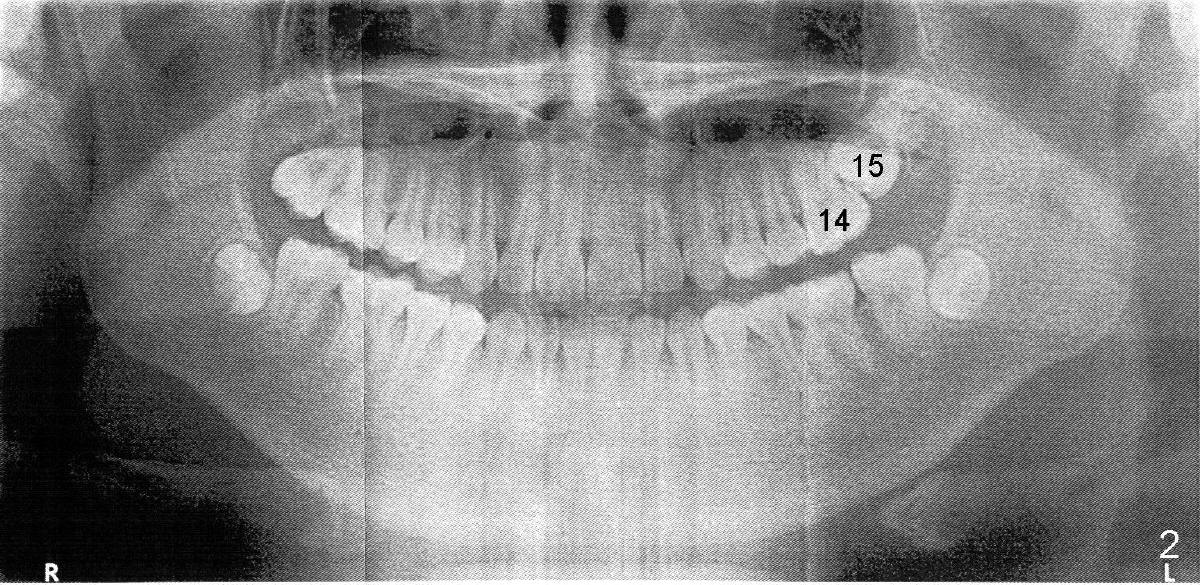

An eleven-year-old Chinese boy presented to my office for new patient exam in 2009.  Panoramic X-ray shows crowded dentition (Fig.1).  Orthodontic treatment was finished by a specialist in 2012.  Post-op X-ray shows that the tooth #15 (upper left 2nd molar) is impacted (Fig.2).  Fig.3 and 4 are magnification of Fig.1 and 2, respectively, demonstrating the change in the axis of #15 from 2009 to 2012 (red line).

Cone-beam CT confirms the impaction of #15 (Fig.5).  The palatal apex is closing.  The asterisk (*) is the tooth bud of #16 (3rd molar).